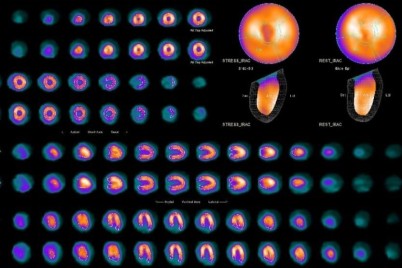

الطائف - هلال اليزيدي نجحت وحدة الطب النووي بمجمع الملك فيصل الطبي بالطائف بفحص أول مسح ذري على عضلة القلب...